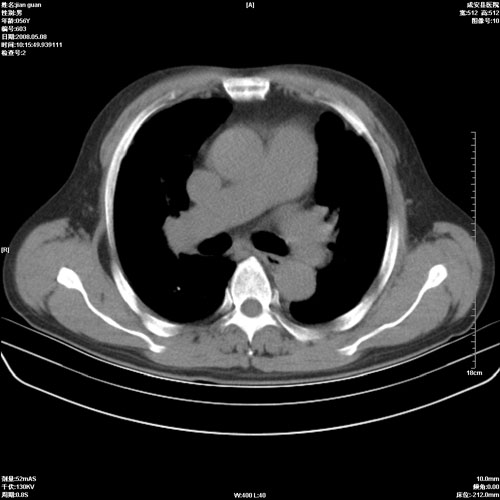

病人 男 60岁 主诉 胸闷 无明显发热 一般情况尚可。

两上肺陈旧性结核;慢支肺气肿、伴感染?

两上肺陈旧性结核;慢支肺气肿

1.两上肺陈旧性结核;慢支肺气肿。

2.肺门血管扩张,心脏增大,为肺心病

考虑.两上肺陈旧性结核;慢支肺气肿。肺心病

两上肺陈旧性结核,慢支肺气肿。

两上肺陈旧性结核;慢支肺气肿。肺肺间质纤维化

两上肺陈旧性结核;慢支肺气肿。